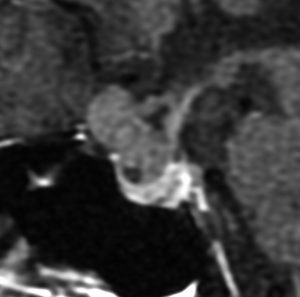

典型的な神経腸嚢胞 neurenteric cyst

左のT2強調画像で等信号,中のT2*で高信号,右はCISS画像です。

T1強調画像では,のう胞周囲の高信号の部分は半固体で,中心部の高信号はドロドロの粘液でした。基本的にガドリニウム増強はされません。まれに薄い膜状に一部が増強されることがあります。

境界明瞭は袋状の腫瘍です。椎骨動脈や脳底動脈を包み込むようにふくらんでいます。